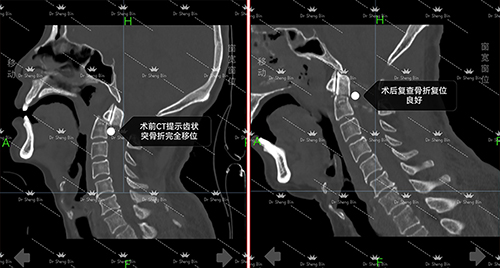

术前、术后影像对比

1122日,家住岳阳的周先生因车祸导致高危颈椎损伤,颈部剧烈疼痛伴随双上肢麻木,整整3天无法正常活动。当地医院束手无策之际,家人紧急将其转送至湖南省人民医院岳麓山院区骨科七病区救治。入院后经检查发现,周先生存在枢椎齿状突骨折,断端已出现错位,且相应层面脊髓受到损伤。

1126日,以盛斌主任为首的手术团队为患者精准实施“枢椎齿状突骨折并脱位切开复位+植骨融合内固定术”。术中,凭借丰富的临床经验和精湛的操作技巧,盛斌主任小心翼翼地将错位的骨折断端成功复位,随后完成了植骨融合与内固定,既重建颈椎稳定性,又最大限度保护脊髓和周围神经组织。整个手术历时2小时顺利完成,出血量极少,达到预期效果。